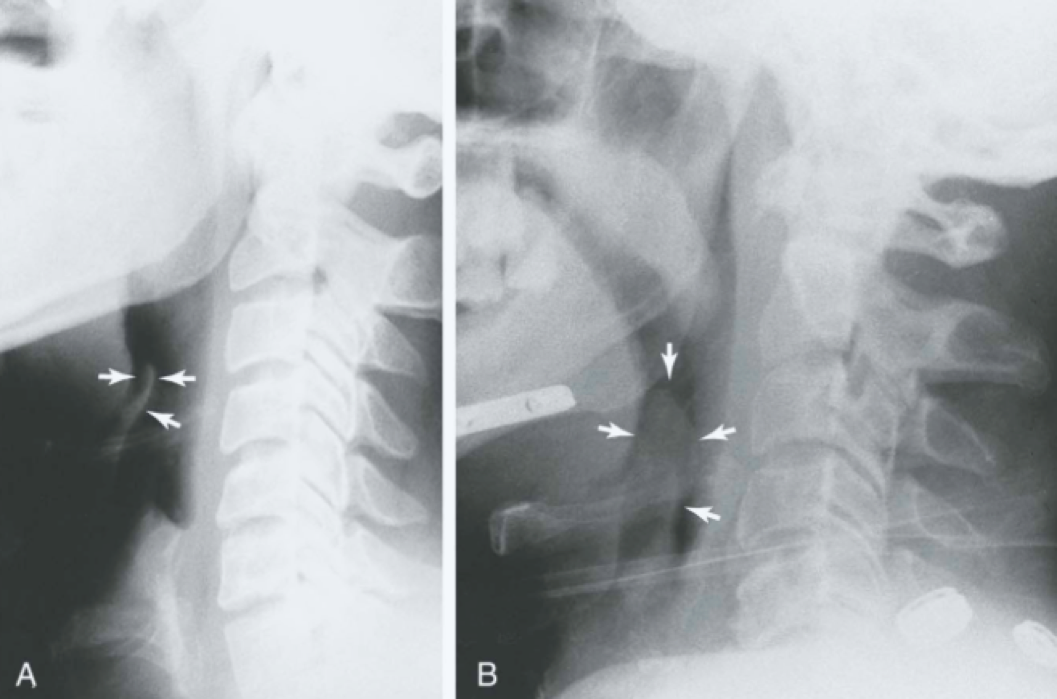

Question 8

Question

In what disease will you see this in?

Answer

• COPD

• Pneumonia

• Epiglottitis

• Croup

• Retropharyngeal Abscess